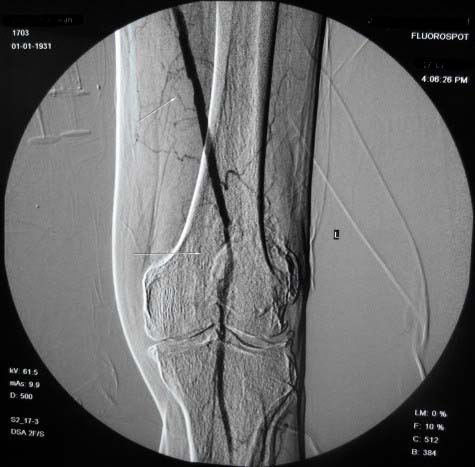

左下肢:

造影方法:取仰卧位,在局麻下,经右股动脉入路,采用改良seldingers技术,置入5f cobra导管于左髂外动脉行dsa,采集速度为2幅/秒,注射速率为6ml/秒,分节段造影;再将导管采用成襻技术放置于右侧髂外动脉,采用左侧同样的方法行dsa,术毕拔管、压迫止血约15分钟,包扎后嘱返病房,术后右足背动脉可扪及搏动。

右侧股浅动脉上、中段多处狭窄,下段闭塞。左侧股浅动脉多处狭窄,国动脉起始部狭窄。可以用球囊扩张配合动脉内溶栓或股浅动脉支架置入。多为糖尿病所致。

双侧股动脉及腘动脉多发狭窄,右股动脉下段闭塞并侧支形成。病变较广泛,球囊可试试,如病人经济不好,最好还是以药物治疗为主。个人意见。